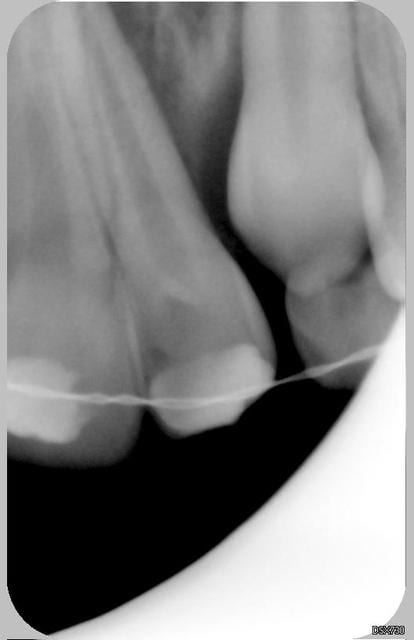

Patiente de 11 ans ayant la 21 expulsée début avril 2006. La dent a été repositionnée en centre de soins. Dans un premier temps, pas de perte de sensibilité. Puis dans un deuxième temps, comme un goût de ça tourne mal avec certainement rhyzalyse interne de la 22 (traitement thermafil pas d'école).

la on est dans un tres beau cas de resorption inflammatoire des 21 et 22

Ci joint la première radio de ces dents avec attelles centre de soins universitaire